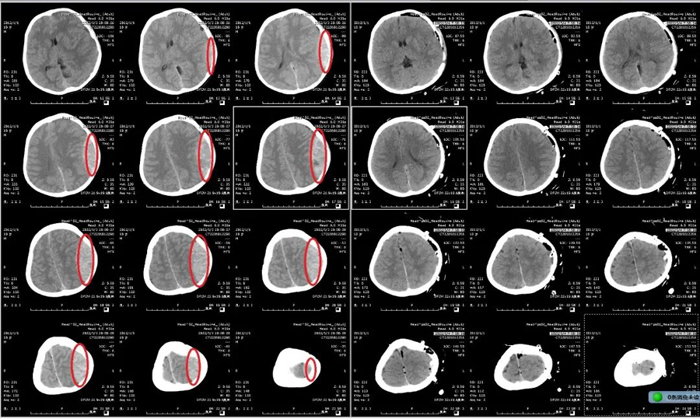

患兒,男,9歲,因“摔傷頭部后神志喪失1小時(shí)余”由120送到我院急診搶救室就診。入院時(shí)患兒昏迷、病危狀態(tài),不能言語(yǔ),一側(cè)瞳孔散大固定,伴一側(cè)肢體偏癱。急診顱腦CT檢查提示:左側(cè)巨大顱內(nèi)血腫,中線移位。急診神經(jīng)外科當(dāng)值醫(yī)師及上級(jí)醫(yī)師綜合評(píng)估病情后,決定立即啟動(dòng)急診綠色通道。

時(shí)間就是生命,對(duì)于神經(jīng)急危重癥患者,每一秒鐘對(duì)于整個(gè)疾病的搶救過(guò)程都彌足珍貴。呂守華主任接到電話后第一時(shí)間來(lái)到醫(yī)院,臨場(chǎng)組織搶救,指導(dǎo)手術(shù)。手術(shù)者蓋大偉主治醫(yī)師以精湛的技術(shù)用時(shí)100分鐘順利完成手術(shù),術(shù)后復(fù)查示顱內(nèi)血腫清除滿意。

顱腦CT術(shù)前、術(shù)后對(duì)比